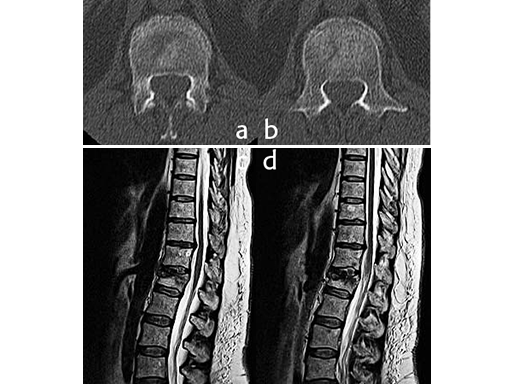

X-rays and CT scans were performed for preoperative analysis, definition of the fracture type and surgical pre-op planning.

The lateral x-ray and CT scans showed a typical wedge deformity of the fractured vertebral body (L1). The fracture included the cranial endplate as well as the anterior and posterior wall.

Additionally, a MRI scan was performed to analyze the integrity of the soft tissue in detail. The lateral MRI clearly showed a ruptured intervertebral disc at the level T12/L1.

Using the USS Fracture MIS system for the initial stabilization allowed for a minimally invasive approach with intraoperative active reduction of the spinal fracture. The unique design of the fracture clamp allowed for independent correction of the sagittal alignment (Fig a) as well as height readjustment (Fig b).